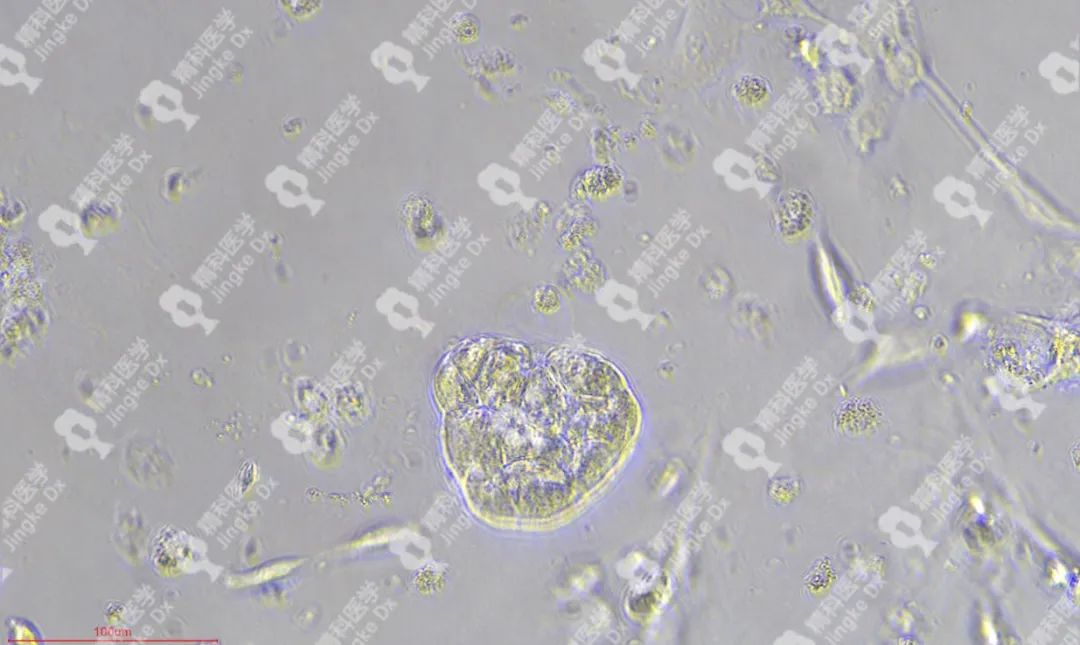

精科類器官培養(yǎng)相關(guān)服務(wù) 精科醫(yī)學(xué)作為類器官技術(shù)轉(zhuǎn)化先行者致力于推動(dòng)類器官技術(shù)的轉(zhuǎn)化與應(yīng)用,對(duì)基于類器官培養(yǎng)擁有成熟的技術(shù)與經(jīng)驗(yàn)。精科類器官團(tuán)隊(duì)技術(shù)深耕十余年,擁有國內(nèi)頂級(jí)的類器官團(tuán)隊(duì),超微量建模技術(shù)成功率高達(dá)95%以上,有成功建模30+種腫瘤的經(jīng)驗(yàn)(包括上述子宮內(nèi)膜癌、宮頸癌和卵巢癌)。可以提供包含類器官建模與保存(建模、凍存、傳代)、類器官檢測(cè)(類器官H&E染色、免疫組化、藥物敏感度篩選)等多種類器官相關(guān)服務(wù)。檢測(cè)服務(wù)最快可在十個(gè)工作日內(nèi)完成,更好為患者爭(zhēng)取治療時(shí)間。 ★ PIC.01 精科卵巢癌類器官圖像 ★ PIC.02 精科宮頸癌類器官圖像 ★ PIC.03 精科子宮內(nèi)膜癌類器官圖像